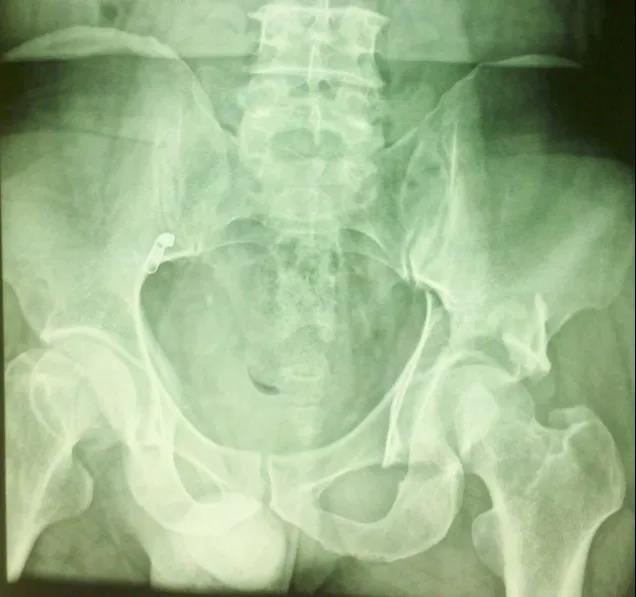

闭孔斜位片:(重点观察前柱、后壁)

髂骨斜位片:(重点观察后柱、前壁)

——髋臼骨折CT检查重要性——

1、显示常规X线不能显示的骨折,有助于诊断;2、可以清楚的显示关节内的碎骨块;3、显示关节面压缩、程度;4、精确显示骨折移位程度;5、定量显示后壁缺损情况;6、有助于术后分析。